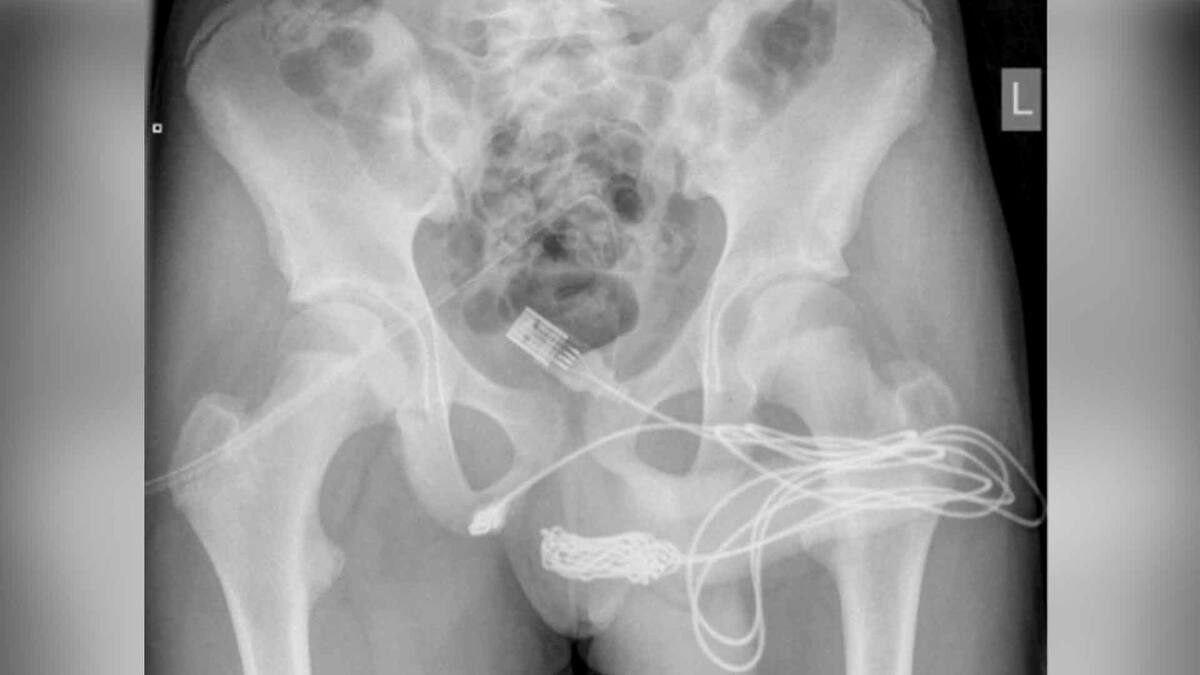

El mayor inconveniente para poder retirar el objeto era el nudo que había hecho el menor con el cable, ya que este permanecía dentro de la uretra a pesar de que los puertos discales de este sobresalían del meato uretral.

Los médicos retiraron primero los puertos USB y, posteriormente, se llevó al paciente a cirugía para realizarle una incisión en los genitales que permitiera extraer la parte del cable que estaba anudada.